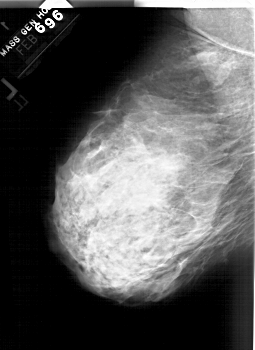

A_1564_1.LEFT_MLO

LEFT_MLO LINES 5941 PIXELS_PER_LINE 4321 BITS_PER_PIXEL 12 RESOLUTION 43.5 NON_OVERLAY